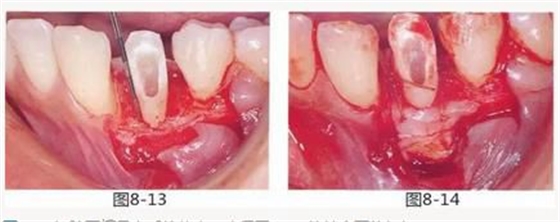

圖8-13 切除牙槽骨之后的狀態(tài)。確保了3mm的健全牙體組織。

圖8-14 為了增加附著齦,進(jìn)行了結(jié)締組織移植術(shù)。